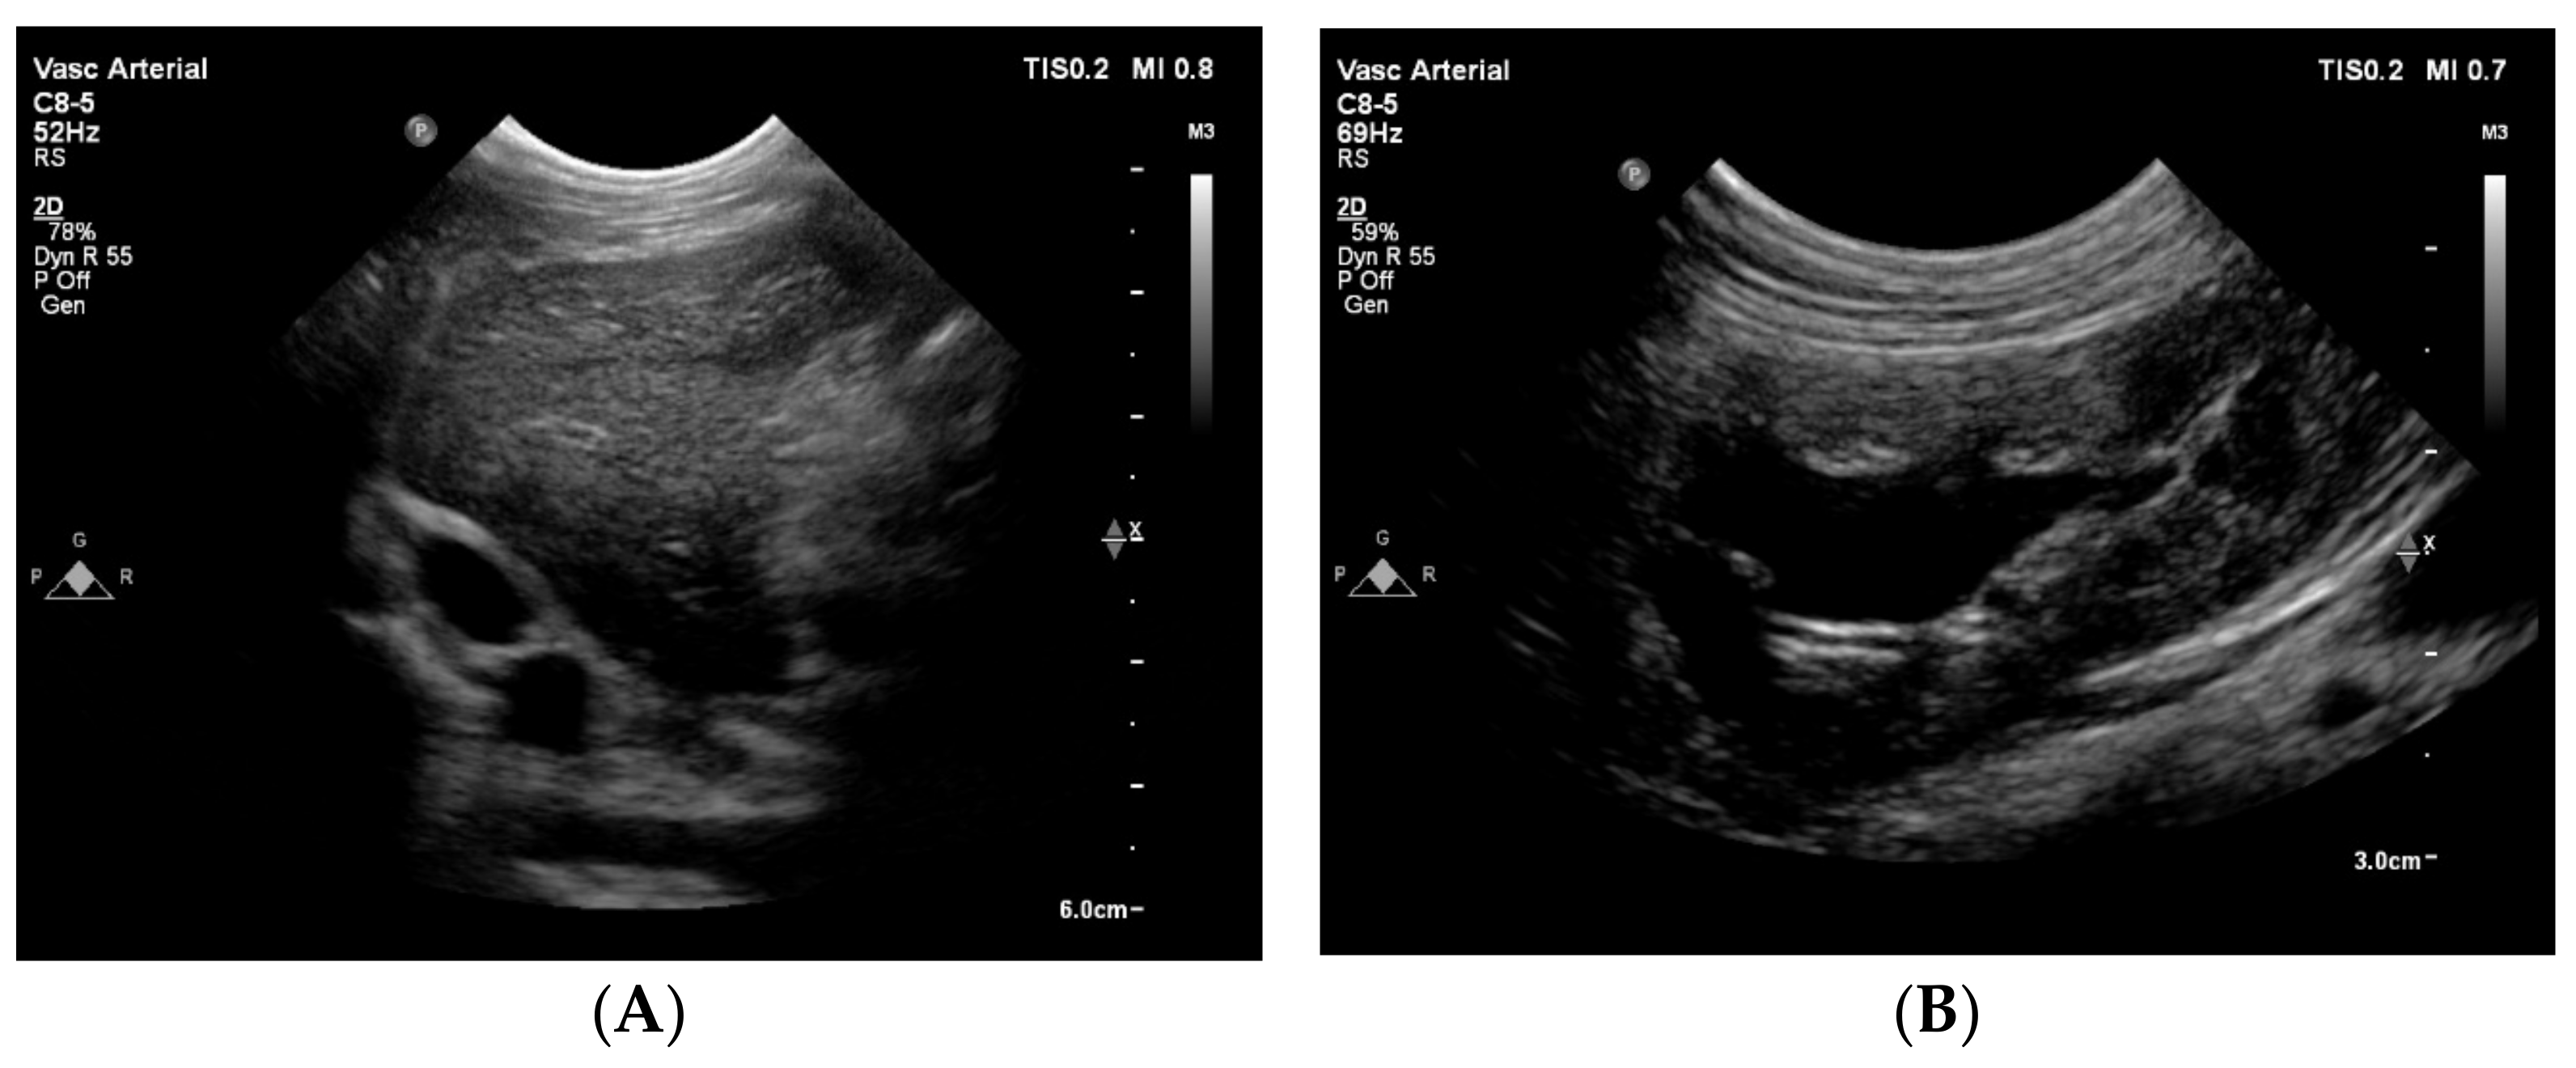

Cross-sectional ultrasound images through an intercostal space at the level of the liver showed no vascular structure at the normal anatomical localization of the CVC, but showed a vein adjacent to the aorta as an oval anechoic structure (Figure 4). The abdominal organs showed no abnormalities, except for a moderate dilation of the left renal pelvis (Figure 4). A computed tomography (CT) was recommended to better understand the anatomy of the congenital anomaly of the large abdominal veins. An obstruction of the venous return from the abdomen was suspected to be the cause of the syncopal episodes and the intermittent underfilling of the heart.

Figure 4. Two-dimensional grey-scale abdominal ultrasound images. (A) The great abdominal vessels in cross-section at the level of the liver obtained through an intercostal space from the right side with the dog in left lateral recumbency. To the left of the image is dorsal, to the right is ventral, to the top is right and to the bottom of the image is the left side of the dog. Dorsal and to the right of the aorta (round anechoic structure), an oval and equally large vascular structure is visible, compatible with an anatomical localization of a dilated (right) azygos vein. At the same time, no vessel can be seen at the location where the caudal vena cava is expected (ventral to the aorta, surrounded with liver tissue). (B) The left kidney displayed in a longitudinal image shows a moderately dilated renal pelvis (~1.7 cm). This finding is compatible with a unilateral ureteral compression or obstruction.